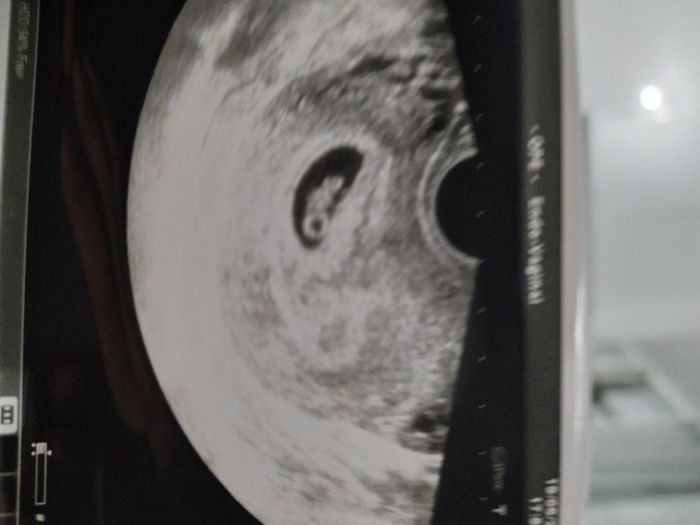

Questa è la mia eco a 7+4, eco interna... Chi ne capisce del metodo ramzi? 🤔